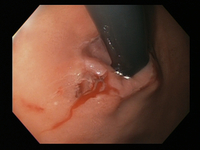

Mallory-Weiss tear

Actively bleeding tear appears as a red longitudinal defect with normal surrounding mucosa

From the collection of Juan Carlos Munoz, MD, University of Florida